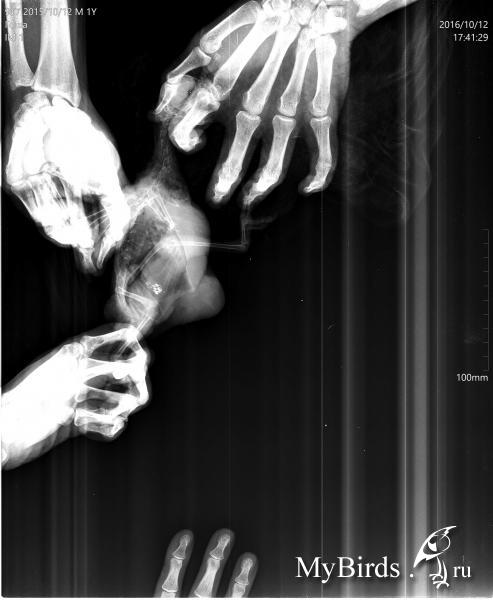

zima543 Опубликовано 12 октября, 2016 Автор #17 Опубликовано 12 октября, 2016 Тут как смогла пыталась сфоткать образование. Оно достаточно большое, с залысиной. Вроде серого цвета. Растекаемости по жердочке не заметила. Помет не видела, видимо, клетку только помыли. Глазки чистые, клоаку не увидела. Птиц дичится. Но не кричит, просто отходит (если так можно сказать о какаду в кенаровской клетульке). Попискивает. Не кричал.Плохо перенес рентген. Там кричал и извивался. Прошу, посмотрите, пожалуйста. Время до принятия решения до завтра. Иначе птицу продадут..

KamaRo Опубликовано 12 октября, 2016 #22 Опубликовано 12 октября, 2016 zima543, снимки очень плохие. На форуме есть статья о рентгене, http://www.mybirds.ru/health/rentgen.phpИ прежде, чем ехать нужно дома потренироваться в раскладке и фиксации.Вот еще статья и примеры как должен выглядеть снимок, http://www.vetruno.ru/articles/?item=67 Вот какими должны быть фото опухоли, http://www.mybirds.ru/forums/index.php?s=&...t&p=1181717 (хотите/не хотите, а нужно собрать волю в кулак, птицу зафиксировать в руках, перо намочить, щеточкой расчесать и в макрорежиме хорошего качества фотографировать).Или вот так, http://www.mybirds.ru/forums/index.php?act...t&id=407436Вот смотрибельное фото липомы, http://www.mybirds.ru/forums/index.php?act...t&id=407464На счет "птица дичится" - это всего лишь трудности. Если хотите какие то рекомендации нужны хорошие фото (читабельные) и читабельный рентген.

zima543 Опубликовано 12 октября, 2016 Автор #23 Опубликовано 12 октября, 2016 Птица не моя. Рентген по моей огромной просьбе делали в лучшей ветклинике города. Я читала как правильно делать рентген. Если хоть какой то шанс понять по этим фото? Больше мне птицу никто не даст для еще одного рентгена. Неужели, все зря?

KamaRo Опубликовано 12 октября, 2016 #24 Опубликовано 12 октября, 2016 Клинка может быть хорошей, но если разложили птицу неправильно и также зафиксировали, то рентген не прочесть.Птица перекошена, часть закрыто рукой. Я поэтому ссылку на статью Маркиной дала - на снимках птицы разных размеров, поп снимкам как будто одного (еще и рентген аппарат настроили, чтобы мелкая птица занимала весь снимок.Окончательный вердикт вынесет Зося, может Александр Томашевский зайдет в тему и тоже свое мнение скажет.Если на нем ничего не прочтут - да, свозили птицу зря и деньги потратили тоже. По фото нет шансов что то понять. Какие должны быть фото я вам ссылки дала.